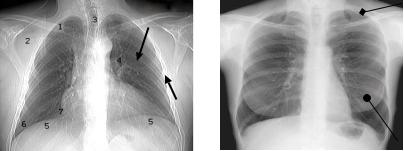

При рентгенографии органов грудной полости теневая картина складывается из суммации всех анатомических элементов по ходу пучка рентгеновского излучения. Рентгеновская картина органов грудной полости в прямой передней проекции представлена на рисунке 1, а рентгеновская картина органов грудной полости в боковой проекции представлена на рисунке 2 с цифровым обозначением анатомических структур.

Рис. 18. Рентгенограммы органов грудной полости мужчины (а) и женщины (б) в прямой проекции.

1 – ключица; 2 – лопатка; 3 – просвет трахеи; 4 – корень легкого; 5 – куполы диафрагмы; 6 – наружный

реберно-диафрагмальный синус; 7 – сердечно-диафрагмальный синус правый.

Передний отрезок ребра обращен выпуклостью книзу (а – нижняя стрелка).

Задний отрезок ребра обращен выпуклостью кверху (а - верхняя стрелка). Ромбовидной стрелкой обозначен контур грудино-

ключично-сосцевидной мышцы (б). Шаровидной стрелкой обозначен контур молочной железы (б)

Структура легочных полей представлена ветвистым рисунком – легочным рисунком, обусловленным сосудами малого круга кровообращения. Тень грудной стенки образована ребрами, мягкими тканями и у женщин молочными железами. Задние отрезки ребер обращены выпуклым контуром кверху, а передние отрезки ребер выпуклым контуром книзу. Интенсивность тени задних отделов ребер превышает интенсивность передних отделов ребер. В области апертуры грудной клетки визуализируется костный скелет верхнего плечевого пояса.